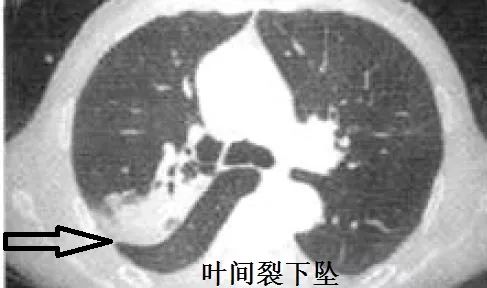

肺炎克雷伯杆菌,是肺炎常见细菌,典型的影像学表现是叶间裂下坠。什么是叶间裂下坠?书上只有文字,我也可以意会到,然而画面很模糊。多年以后,我才突然秒懂!

叶间裂下坠,从CT上看,就感染的肺组织膨胀了!

肺炎克雷伯杆菌,就是这么骄傲的细菌,非常喜欢自我膨胀!控制不住的自我膨胀!

最后,再来回望一下,什么是叶间裂下坠。